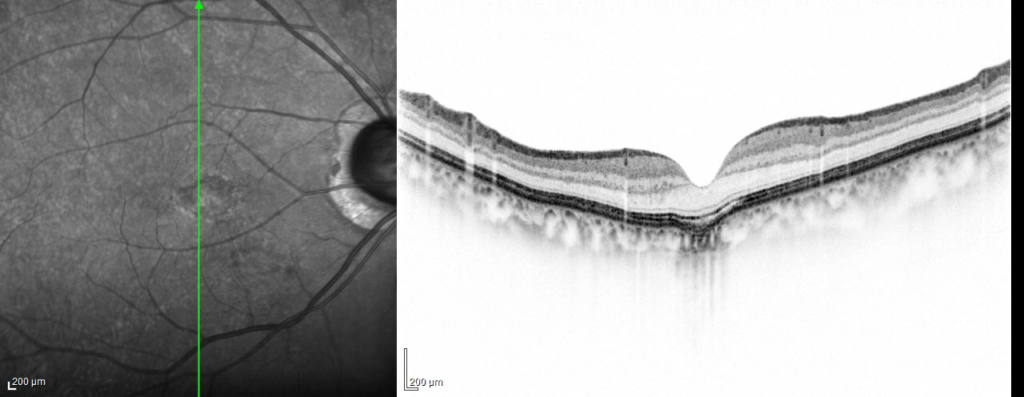

conforming typeとnon-conforming typeがあります。